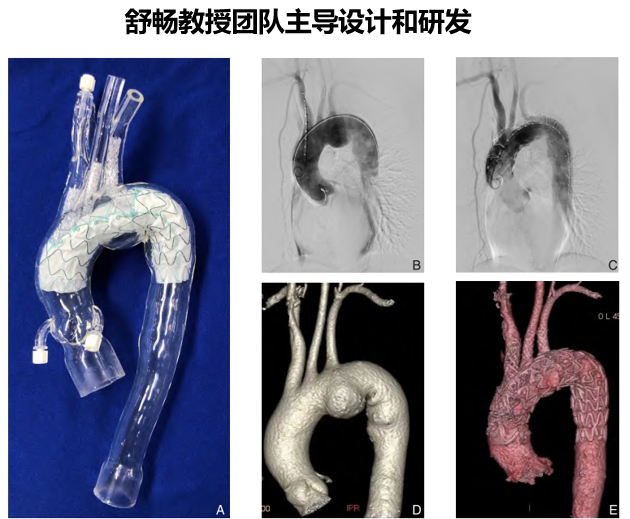

C-S全主动脉弓覆膜支架系统具有以下特点和优势

(1)操作简单可靠——凹槽支架一体式设计操作简单,手术时长短,可有效重建血管并隔绝病变;

(2)安全从容一一主体释放后可确保弓上分支血管通畅,供血不受影响,医生可从容进行分支重建;

(3)性能优异选择广泛一一分支支架性能优异,规格多样可适应不同弓上分支,植入后形态良好,具有较小输送系统外径,使用方便顺畅;

(4)使用灵活——根据病变的不同,可灵活选择搭配“主要模块+选配模块”组合。